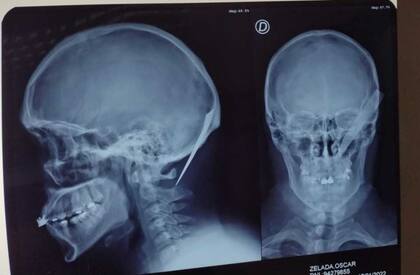

Herido, el joven fue trasladado por la Policía al hospital de Puerto Madryn donde le realizaron una radiografía para determinar la lesión que le provocó la puñalada en su cabeza y en la imagen se aprecia con claridad cómo la hoja de unos diez centímetros quedó atravesada sobre la nuca, en proximidades de su oreja derecha y sin el mango.